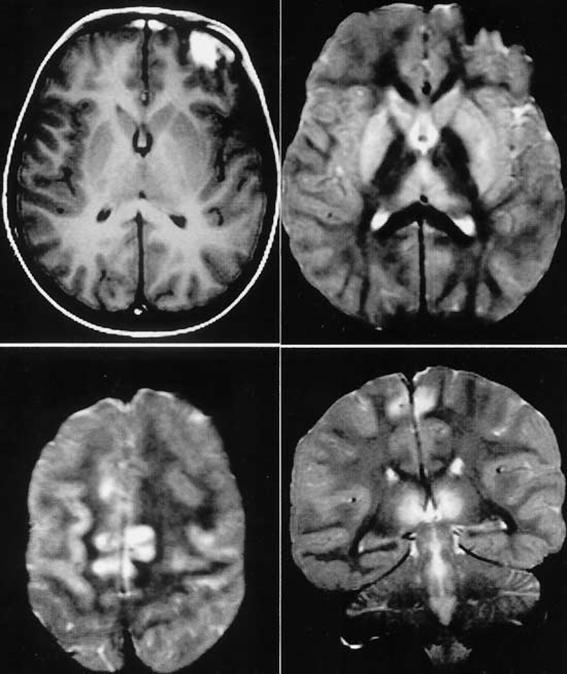

女,13歲,急性髓性白血病化療后持續(xù)性惡心、嘔吐,臨床表現(xiàn)為眼球震顫、眼肌麻痹、意識障礙。顱腦MRI提示雙側對稱性丘腦、殼核、尾狀核及皮層異常信號。